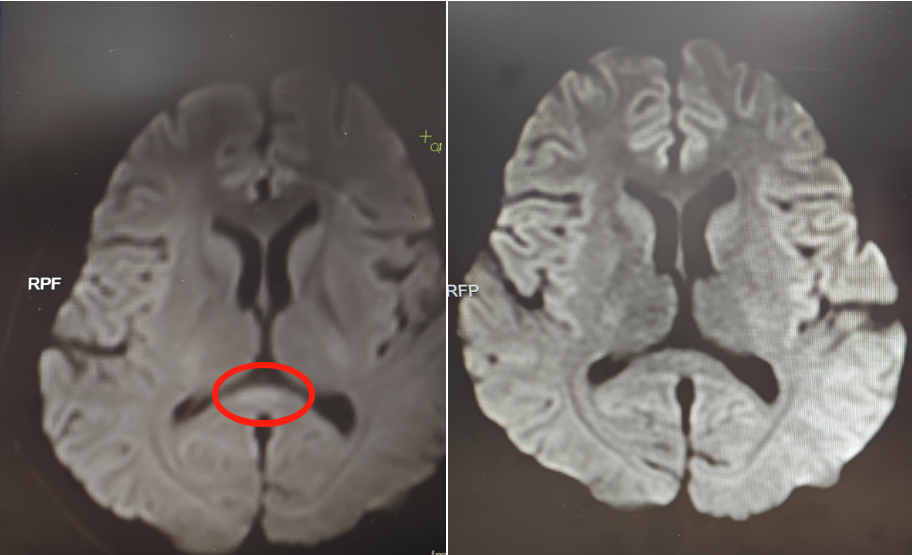

该院神经内六科医生接诊后,初步判断为脑炎。完善血清、脑脊液检测等,结果不支持颅内感染及自身免疫性脑炎,进一步完善细胞因子等炎症指标,结合核磁共振等,最终诊断阿婷为副感染性脑病。

▲治疗前(左)核磁共振提示胼胝体压部病变